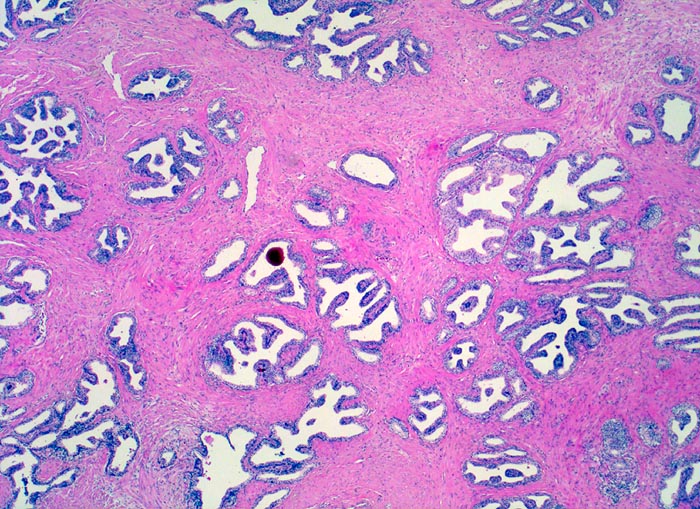

• Herde kleiner Karzinomdrüsen ohne Basalzellschicht.

• Fehlende lobuläre Anordnung der Karzinomdrüsen.

• Konfluierende Drüsen bilden kribriforme Muster.

• Karzinomzellen mit stark erhöhter Kern-Zytoplasmarelation und hyperchromatischen Zellkernen mit grossen eosinophilen Nukleolen.